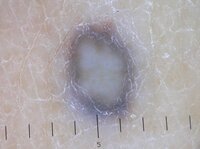

Hypopigmented areas (structureless/ homogeneous), Central Hypopigmented Pattern, Central white patch

Признаку соответствует наличие довольно обширной, не менее 10% от общей площади образования, зоны депигментации (степень депигментации может быть различной), расположенной в центральной части образования. Границы этой зоны размытые, но чаще всего пятно имеет правильную округлую форму. В дерматофибороме белесый центр часто сочетается с наличием по периферии образования нежной мелкоячеистой пигментной сети (случай, когда в немеланоцитарном образовании встречается признак, характерный для пигментных опухолей). Данный признак является специфическим для дерматофибромы, хотя центрально расположенные зоны депигментации могут обнаруживаться и в пигментных невусах.